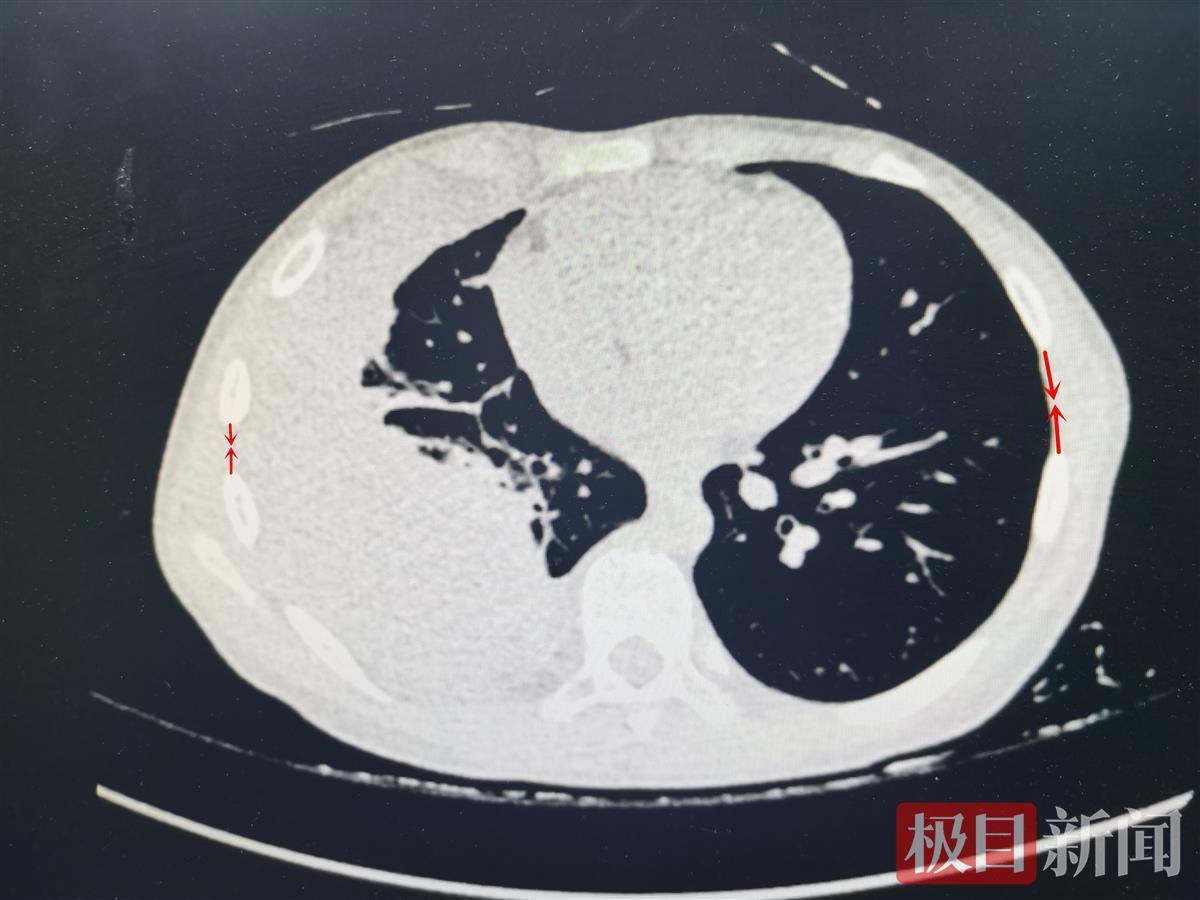

检查发现,田田的结核性脓胸已经相当严重,在他的胸腔壁与肺组织之间,因感染结核杆菌形成的复杂性粘连已经纤维化,这些纤维板把肺紧紧包裹,让呼吸受限。同时,纤维板收缩、变形,牵拉着周围的脊柱、肋骨、膈肌,让他脊柱弯曲,肋骨变形,膈肌僵化,又进一步压缩胸腔空间。

武汉市肺科医院外科主治医师刘小玉说,田田这么小的年龄就患有这么严重的结核性脓胸,实属少见。12月10日,刘小玉采用单孔胸腔镜解决结核性脓胸技术,为田田手术剥离了纤维板,成功为肺解除封锁。脊柱、肋骨、膈肌也都得到了释放。